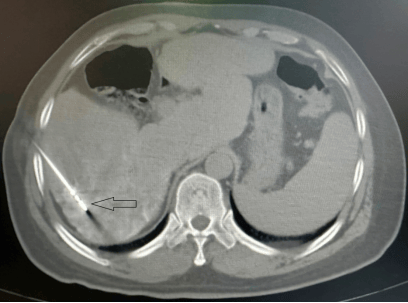

【佑安援藏】大病不出藏,北京佑安医院援藏专家李建军助力拉萨市人民医院开展首例肝癌微波消融术

患者是一名56岁藏族男性,因“丙肝史6年,发现肝占位10天”入院。患者既往有丙肝史,予抗病毒治疗后好转。10天前在外地医院查核磁发现肝内占位,考虑肝癌可能,建议行手术切除治疗,但患者拒绝。遂转诊至拉萨市人民医院援藏专家李建军主任医师门诊,李主任结合患者病史及影像资料,认为肝癌诊断明确,建议患者行肝动脉化疗栓塞术序贯肝肿瘤微波消融术。但患者不放心拉萨市人民医院的设备和医疗水平,执意想去北京治疗。李建军主任耐心地和患者解释,说明医院使用的是目前国内最先进的医疗设备,同意亲自为患者手术,并说明消融术是一种根治性治疗方法,和外科手术切除、肝移植一样都是肝癌的三大根治性治疗方法之一,且具有微创、费用低、术后恢复快等优势。患者及家属欣喜同意住院治疗。

图1 红色圆圈内为肝癌病灶